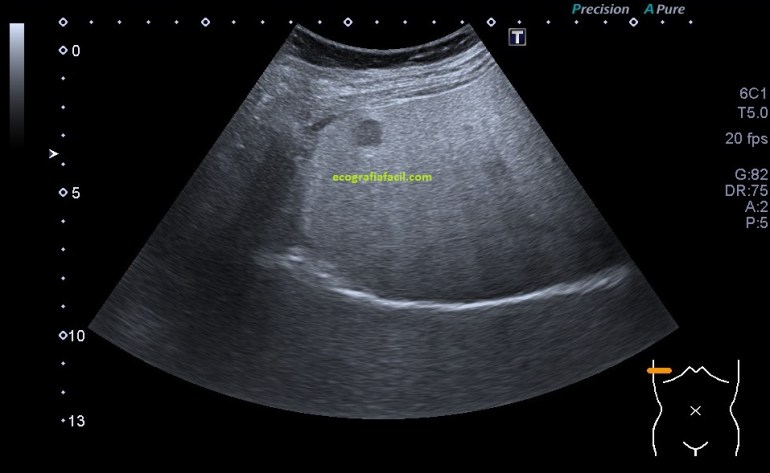

- Suelen ser lesiones solitarias, habitualmente isoecógenicas con el parénquima hepático. Formas atípicas de presentación presentan hipoecogenicidad o hiperecogenicidad.

En las imágenes puedes ver una LOE hepática que es cumple muchos criterios de los que hemos señalado arriba, pero el de la semiología, que es de los más importantes, no lo cumple. Se habla de que la HNF es una lesión isoecogénica con el parénquima hepático, ésta LOE es evidentemente hipoecogénica.

La paciente cumplía el resto de los requisitos, la edad y contestó afirmativamente cuando fue preguntada si tomaba o había tomado anticonceptivos vía oral, pero la LOE, era hipoecogénica…

Finalmente la Radióloga informó la lesión como HNF aún siendo marcadamente hipoecogénica, si te fijas bien en las imágenes, sobre todo en la imagen 3, donde se observa el riñón derecho, verás que existe una marcada hiperecogenicidad hepática en relación con el riñón derecho, que como muy bien sabes, deben ser isoecogénicos.

La paciente por tanto padece una esteatosis hepática, la lesión es hipoecogénica con respecto al parénquima hepático infiltrado de grasa, pero isoecogénica con el patrón ecográfico de la corteza renal, donde quiero ir a parar es a que la LOE de HNF sería isoecogénica con el parénquima hepático si eventualmente, éste, estuviese sano, es decir, si no estuviese infiltrado de grasa.